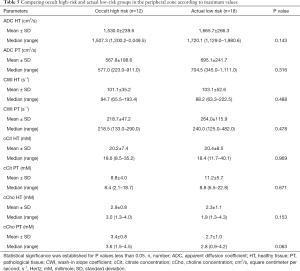

The MRI data classified 9 (34.6%) patients as T2 MRI and 17 (65.4%) patients as T3 MRI. Mean values, SDs, median ADC and CWI values, and citrate and choline concentrations for targeted zones of interest in healthy and pathological tissue are displayed in Table 1.

Topographic MRI data from the post-operative LR (n=8) and HR (n=18) patient groups showed a high proportion of T3 MRI findings (77.8% vs. 37.5%) in HR patients (Tables 1,2).

The mean abnormal ADC values were markedly lower in the HR group than in the LR group, although the difference was not statistically significant (P=0.06). However, cCho mean values were significantly higher among HR patients (3.6 vs. 2.2; P=0.001).

We observed that ADC and cCho values were within the same range as in the previous group, with choline levels significantly higher among HR patients (Table 3).

Analysis of the PZ

In the PZ, choline levels were consistently significantly higher in patients with occult HR, as well as in the pre-operative HR group compared to the pre-operative LR group (cCho, 3.1 vs. 2.2; P=0.020; and 4.1 vs. 2.7; P=0.013, respectively) (Tables 4,5).

Citrate values were always higher, regardless of the compared groups, although the difference was not statistically significant.

The steep decreasing ADC trend was confirmed among patients identified as pre-operative HR, as well as among occult HR patients. However, the difference was not statistically significant.

Regardless of the compared groups, CWI showed no significantly discriminating values between the risk groups, despite a slightly faster rise among HR patients (264.0 vs. 218.7 s−1).